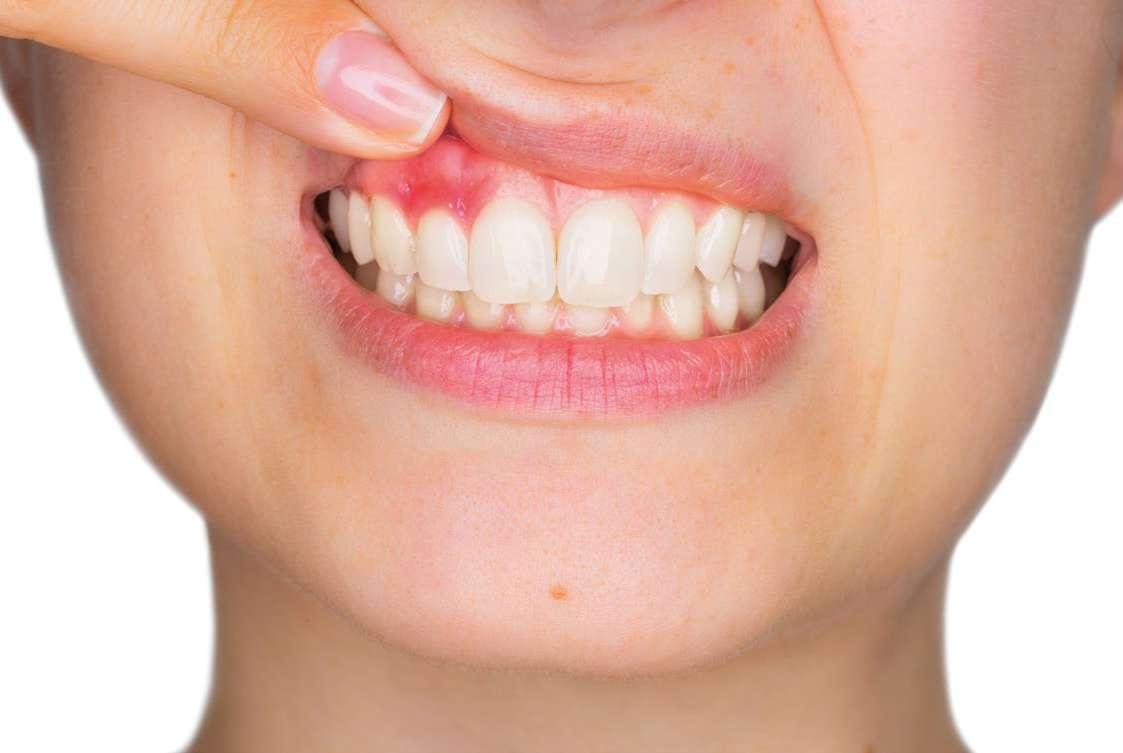

na paciente de 35 años (Figura 1) fue remitida a la Clínica de Odontología Reconstructiva de la Universidad de Zúrich debido a una infección crónica en el diente 11 y con expectativas estéticas muy altas. El diente 11 había sufrido un trauma hace 10 años y había sido tratado con multiple endodoncias sin éxito. El diente presentaba un absceso bucal (Figura 2), una bolsa periodontal aislado de 9 mm, y una ausencia de la tabla vestibular ósea (Figura 3). El diagnóstico se estableció como una fractura radicular vertical, lo que resultó en un pronóstico pobre. El plan de tratamiento consistió en una extracción combinada con preservación alveolar, colocación de implante diferido con injerto de tejido conectivo, una corona cerámica implantosoportada en 11 y una nueva carilla de cerámica para el diente 21.

El diente 11 fue extraído (Figura 4), seguido por la preservación alveolar. Se realizó un injerto pediculado de espesor parcial rotado del paladar (Figura 5), junto con una membrana de colágeno reabsorbible, un xeno-injerto bovino y cianoacrilato sellando al alveolo (Figura 6). La provisionalización consistió en un puente adhesivo de resina con dos alas de metal. El alveolo se dejó cicatrizar durante 6 meses, después de los cuales se tomó una impresión digital así como un escáner CBCT (Figura 7). Se llevó

a cabo una planificación digital para una cirugía guiada de implante en una posición protéticamente ideal (Figura 8). El implante 11 se colocó completamente guiado a través de una férula (Figura 9). Las dimensiones del reborde alveolar eran ideales para la colocación del implante en una posición atornillada (Figura 10), al igual que la calidad del hueso cicatrizado. Un injerto de tejido conectivo subepitelial fue estabilizado ocluso-bucalmente al implante (Figura 11) y el puente adhesivo fue recementado (Figura 12). Después de 3 meses de cicatrización, se realizó una restauración provisional y se acondicionó adecuadamente para dar forma al perfil de emergencia, imitando el del diente adyacente (Figura 13). Después de una fase provisional, se tomó una impresión analógica individualizada para el implante 11 y el diente 21 (Figura 14). El laboratorio fabricó una corona implantosoportada de zirconio con cerámica estratificada para el 11 y una carilla laminada feldespática para el diente 21 (Figura 15). Ambas restauraciones fueron colocadas en la paciente y mantenidas. La paciente quedó muy satisfecha con el resultado estético de las restauraciones (Figuras 16, 17). Después de 2 años, el implante permanece saludable con el hueso marginal estable (Figura 18) y una buena calidad y cantidad de tejido blando.